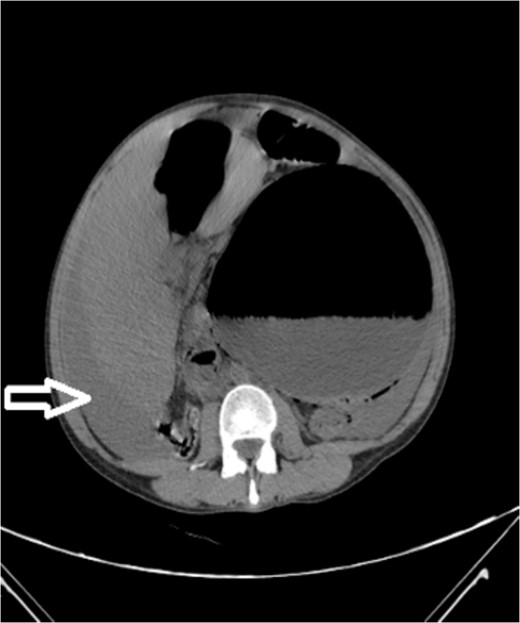

Upon admission to our hospital, the patient’s physical examination revealed hypotension (87/52 mmHg) and tachycardia (150 bpm), along with marked diffuse abdominal tenderness and guarding. Laboratory investigations indicated a hemoglobin level of 7.1 g/dl, a white blood cell count of 14.5 × 103 μl, and a platelet count of 202 × 103 μl. An abdominal CT scan without contrast showed an enlarged ectopic spleen measuring 18 cm in the right abdominal area, a distended stomach, a moderate volume of hemoperitoneum, and significant intra-abdominal fluid accumulation. CT findings are shown in Figs 1–3. Based on these findings, the patient was immediately transferred to the operating room.

Noncontrast coronal CT scan of the abdominopelvic area showing the spleen located in the right upper abdominal area.